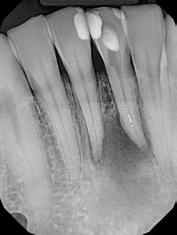

A pácienst a két alsó középső metszőfog (31, 41) gyökérkezelése céljából irányították dr. Witkowski rendelőjébe

(2. ábra). A kiindulási vizsgálatot követően megkezdődött a páciens endodonciai ellátása (3. ábra). A jobb alsó kismetszőfogat (41) a beutaló orvos már előzetesen megtrepanálta (4. a. ábra), így csak a bal alsó fogban (31) kellett a hozzáférési nyílást kialakítani (4. b. ábra). A jobb alsó fogban lévő gyökércsatornát ISO #25 gyökércsúcsi átmérővel rendelkező 4%-os konicitású gyökérkezelő tűvel (25/.04), míg a bal alsó fogat egy mérettel kisebb (20/.04) eszközzel tágítottuk fel (VDW.ROTATE;VDW) (5. a–c. ábra). A gyökércsatorna átöblítése során lézeres aktiválást végeztünk Er,Cr:YSGG lézerkészülék (Biolase) segítségével (1,5 W, 100 Hz), majd a csatornákat előkészítettük a végleges gyökértömés befogadására. A jobb alsó fogban (41) CSBS sealert és egy poén technikát alkalmaztunk, míg a bal alsóban (31) dugattyú technikával készítettük el a gyökértömést (6. a–e. ábra). A gyökértömés behelyezését követően egyből kontrollröntgent készítettünk (7. ábra). A hat hónappal később készített kontrollfelvételen jól megfigyelhető volt a periapikális lézió gyógyulása (8. ábra)